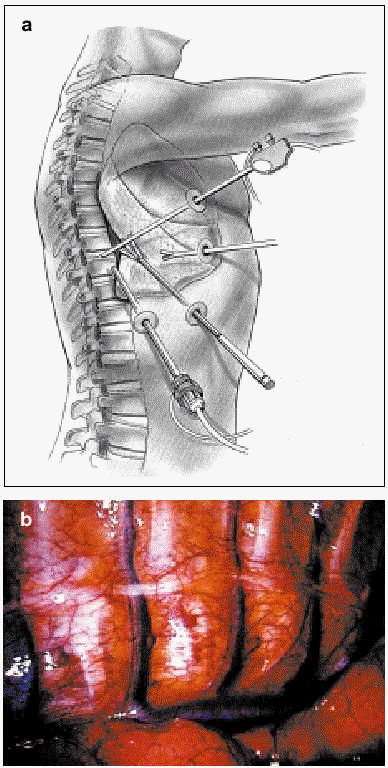

Thoracoplasty

Thoracoplasty consists in a partial resection of the ribs of the convexity of the curve (Figures 2 and 3). The main aim is to improve appearance. Thoracoplasty has also been described in the context of instrumentation performed through a posterior route. When this technique is used as a complement to vertebral fixation, a high number of peri- and postoperative complications (pneumothorax) occur, with altered respiratory mechanics during the first 2 months (decline in lung volume of 12% to 16%). Some authors attribute part of this decline to postoperative pain.13 However, 2 years after surgery, respiratory function has returned to its preoperative status.

Figure 2. Schematic depiction of thoracoplasty.